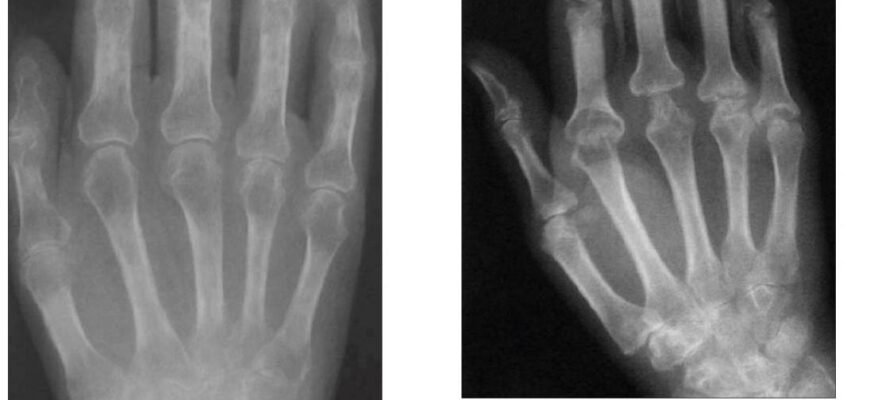

| Рентгенографія | Поширений метод діагностики, що дозволяє візуалізувати кістки та їх ураження. |

Як розпізнати кістково деструктивні зміни це? Є кілька симптомів та методів діагностики, які можуть допомогти.

- Деформація кісток або суглобів.